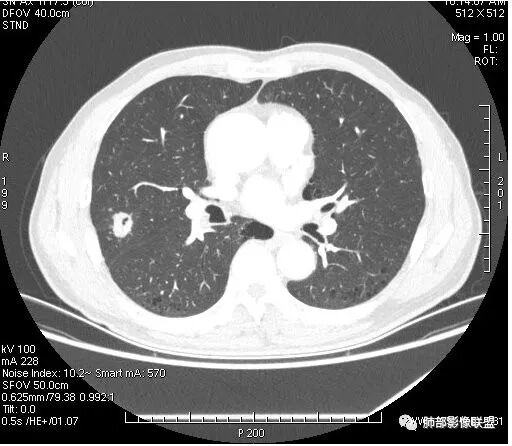

我们从外朝内,肺气肿背景

有毛刺吗?长?粗短?胸膜牵拉?

细毛刺,

有,长短都有,短的为主

细毛刺,胸膜牵拉

有分叶吗?

边缘是不是有些地方膨隆?

有空泡征,实性部分密度均匀?强化均匀?

内部血管怎么样?

支气管?

有血管穿行

部分地方膨隆,血管进入增粗

走行比较自然,破坏不明显,支气管没看见进去,不知道到底有没有

支气管堵塞

支气管截断明显啊,南大不指出,我没看出来。

右肺上叶结节,周围毛刺明显,其内有小炮征,分叶,强化中度,其内可见坏死,支气管有截断,考虑腺癌,鳞癌待排。病灶的上缘有一个小支气管进入,然后截断了

有卫星灶

但我怎么看这些毛刺还是偏硬呢